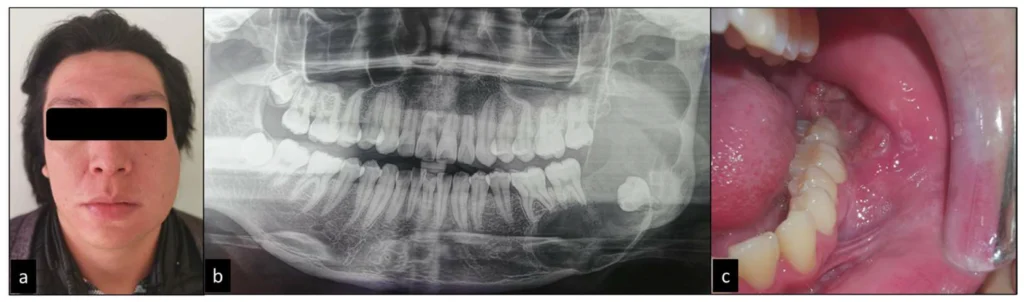

• Secara radiologis (hasil rontgen atau CT scan), menunjukkan gambaran khas:

• Multilokuler (“soap bubble” atau “honeycomb appearance”) — tampak seperti gelembung sabun di dalam tulang.

• Dapat juga tampak unilokuler (rongga tunggal) terutama pada lesi kecil.

• Pembengkakan rahang yang progresif dan tidak nyeri.

• Perubahan bentuk wajah atau asimetri.